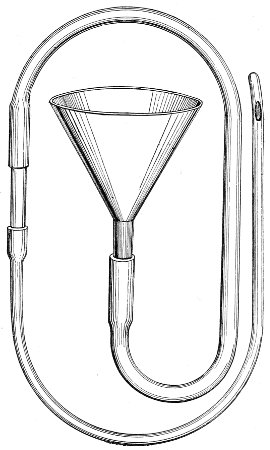

The woman should be kept as quiet as possible. The bowels should be moved freely with saline purgatives. She should take, three times in twenty-four hours, lying upon her back, a vaginal douche of one gallon of a boracic-acid 51 solution (ʒj to the pint). The temperature of the solution should be about 110° F.

If the disease be of gonorrheal origin, a warm bichloride solution (1:5000) should be used in the same way.

After the acute symptoms have subsided local applications should be made, in addition to the douches. The woman should be placed in the knee-chest position, and the vagina should be thoroughly exposed with the Sims speculum. If necessary, the vaginal surface should be gently cleaned with warm water and cotton. A 4 per cent. solution of cocaine may be applied to the vagina if there is much pain. Then the entire vaginal surface should be painted with a solution of bichloride of mercury (1:1000). These applications should be made daily until the disease is cured. The vaginal douches should be continued at the same time.

In the chronic form of the disease and in senile vaginitis the local patches of inflammation should be painted once a day with a solution of nitrate of silver, 5 to 10 per cent., or stronger if the condition does not yield. The senile form of vaginitis, being dependent upon a general condition, is often impossible to cure. We can sometimes relieve the discomfort by applying boracic-acid ointment (ʒj to ℥j) to the vagina. The application of pure carbolic acid to the inflamed patches sometimes does good.